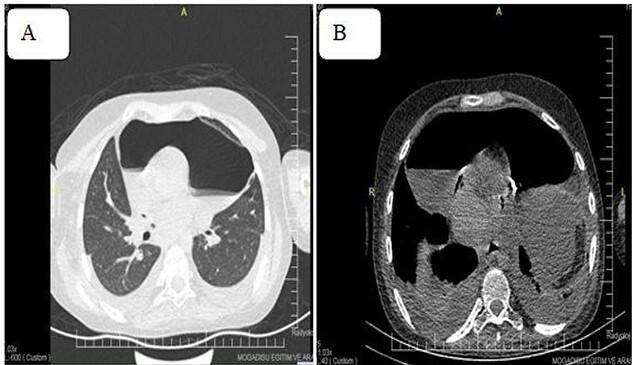

Constrictive pericarditis is an uncommon complication of acute pericarditis, mainly caused by non-idiopathic sources. Pneumopericardium is the presence of air in the pericardial sac resulting from various procedures and circumstances, including trauma, iatrogenic, non-iatrogenic and natural causes. Here, we report a 16-year-old girl who came to the cardiology outpatient complaining of weakness, abdominal distention and shortness of breath while lying down and exertion. An echocardiography evaluation revealed a thickened precordium and massive pericardial effusion. Pericardiocentesis was performed for diagnosis and treatment purposes. Despite the patient's remaining symptomatic and having no improvement following the procedure, we decided to perform chest computed tomography, which revealed a thickened pericardium with pneumopericardium. Partial pericardiectomy was performed successfully, and the sample was sent to the pathology department, which confirmed tuberculous constrictive pericarditis. The patient's symptoms improved, and she was discharged on postoperative Day 5 standing on her foot.

缩窄性心包炎是急性心包炎的一种罕见并发症,主要由非特发性病因引起。心包积气是指心包腔内存在气体,其由各种操作及情况导致,包括创伤、医源性、非医源性及自然原因。在此,我们报告一名16岁女孩,她因平卧及活动时出现乏力、腹胀和气短而前来心脏科门诊就诊。超声心动图评估显示心前区增厚及大量心包积液。为诊断和治疗目的进行了心包穿刺术。尽管患者术后仍有症状且无改善,但我们决定进行胸部计算机断层扫描,结果显示心包增厚并伴有心包积气。成功实施了部分心包切除术,样本被送至病理科,病理结果证实为结核性缩窄性心包炎。患者症状改善,术后第5天自行出院。